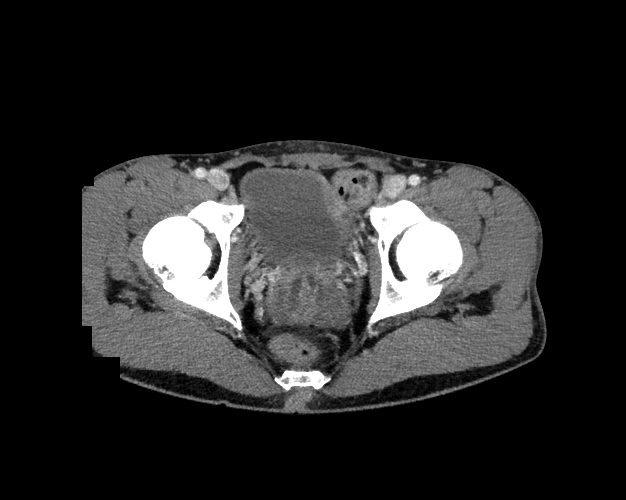

Pelvis

Covers pelvic MRI anatomy.